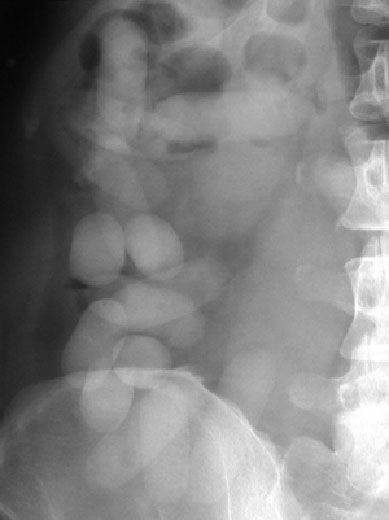

SIGNO DEL DOBLE CONDÓN

En la radiografía simple de abdomen, la presencia de bolas de narcóticos colocadas dentro de preservativos en el colon dan una apariencia de anillos muy típicos. En este ingenioso sistema de transporte, la bola de narcótico es envuelta por dos preservativos, cada uno de los cuales está plegado tres veces sobre sí mismo. El aire atrapado entre cada una de las capas de los preservativos produce una imagen radiolúcida patognomónica.

No tenemos ninguna imagen de este signo, ya que en nuestro medio las bolas de hachís no se introducen en preservativos, sino en bolsitas de plástico, que sí se ven en la imagen superior.